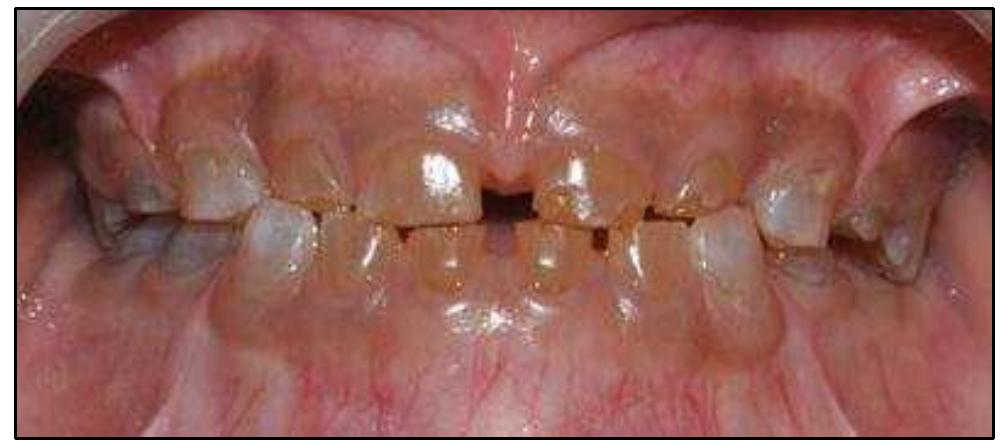

Essa alteração compromete a estrutura e a qualidade da dentina, resultando em dentes com aspecto opalescente, coloração variando entre acinzentada, amarelada e marrom, além de maior fragilidade mecânica.

As manifestações da dentinogênese imperfeita podem variar em intensidade, mas algumas características são recorrentes:

- Alteração de cor: dentes opalescentes, acinzentados ou amarronzados.

- Maior fragilidade: fraturas coronárias e desgaste acentuado.

- Atrição precoce: perda rápida de altura dentária funcional.

Essas alterações não são apenas estéticas, mas também funcionais, já que comprometem a mastigação, favorecem a sensibilidade dentária e aumentam a necessidade de intervenções protéticas precoces.

É a forma mais comum, não associada à osteogênese imperfeita.

Afeta tanto a dentição decídua quanto a permanente, sendo frequentemente identificada em pacientes sem histórico de doenças sistêmicas.

Clinicamente, apresenta dentes opalescentes e radiograficamente câmaras pulpares obliteradas.